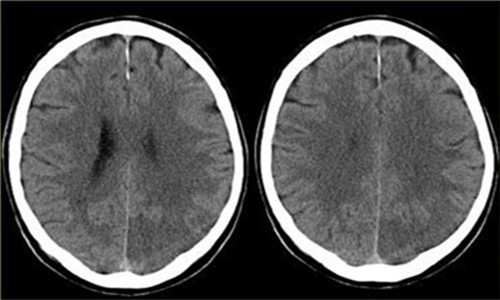

脑梗塞的检查非常多 , 一定要根据当时的具体情况进行具体的对待 。

一般来讲 , 如果是筛查的话 , 最常做的就是颈部血管彩超 , 以及经颅多普勒这俩检查 , 基本上可以大体的反应颈部血管以及颅内血管的一个最基本的形态 , 也是常规的检查 。 花费比较少 , 出结果也相对较快 , 结果的可行性也相对较好 ,

如果确实有一定的问题 , 那么 , 则继续进行下一步的检查 。

一般就是要做头部的CT , 或者是头部的核磁检测 , 这样可以看到颅内是否产生了一定的病变性质 , 比如说脑梗死以及脑梗死的大小 , 位置 , 还有周围一些相应的组织关系 。